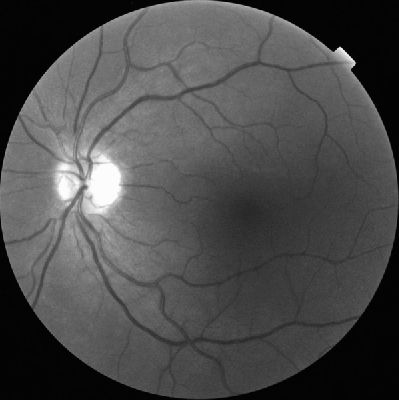

GIF of Nerve fibre loss by Badabing